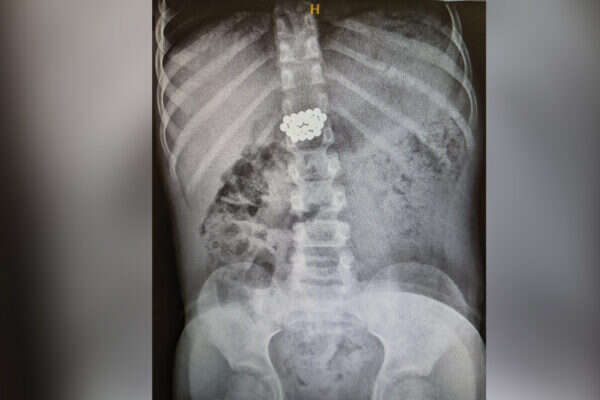

ד"ר אייל זיפמן, מנהל השירות לגסטרואנטרולוגיה ילדים מסביר כי בגלל ההבנה שהמגנטים עלולים לחולל נזק - והחשש מנקב במעי וזיהום בחלל הבטן, הוחלט לשלוח את הילד באופן מידי לצילום. "בצילום נצפו המגנטים במעי הדק במקום שלא ניתן להגיע ללא ניתוח", סיפר ד"ר זיפמן. "הוחלט כי נעשה מעקב לבחון את מקומם ובשלב מסוים נמצא כי הם אינם מתקדמים לבד ויש לעשות קולונוסקופיה. המגנטים נמצאו במעי הגס והוצאו בהצלחה".